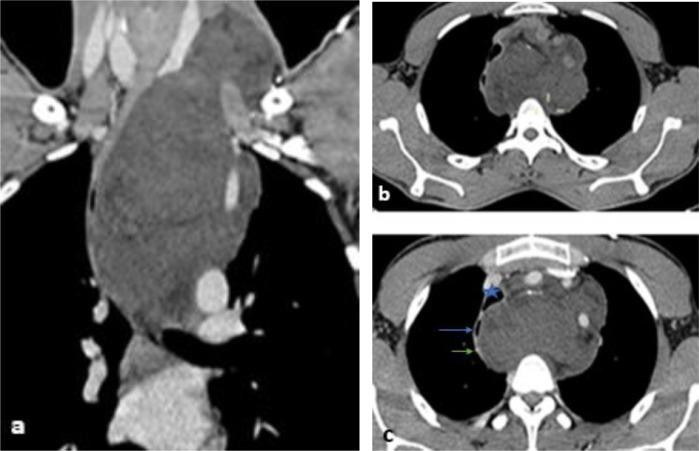

Low-grade fibromyxoid sarcoma (LGFMS) is a rare tumor characterized by bland histological features and aggressive clinical course, it is a distinctive variant of fibrosarcoma with high metastasizing potential and sometimes a long interval between tumor presentation and metastasis, the most common anatomic locations of occurrence are the lower extremities, thorax, inguinal area, and upper limbs, Here, we present the case of a 29-year-old patient with a deceptively benign-appearing mass arising in the mediastinum that had been discovered on computed tomography, a biopsy under cervicotomy was performed and histopathological examination revealed low-grade fibromyxoid sarcoma. In conclusion, LGFMS can arise in the mediastinum, and physicians should consider this entity as a differential diagnosis in the presence of such mass.

低度纤维黏液样肉瘤(LGFMS)是一种罕见肿瘤,其组织学特征平淡,但临床过程具有侵袭性。它是纤维肉瘤的一种独特变体,具有高转移潜能,有时肿瘤出现与转移之间间隔时间较长。最常见的发病解剖部位是下肢、胸部、腹股沟区和上肢。在此,我们报告一例29岁患者,其纵隔出现一个看似良性的肿块,通过计算机断层扫描发现,经颈部切开活检,组织病理学检查显示为低度纤维黏液样肉瘤。总之,LGFMS可发生于纵隔,医生在遇到此类肿块时应考虑将该实体作为鉴别诊断之一。